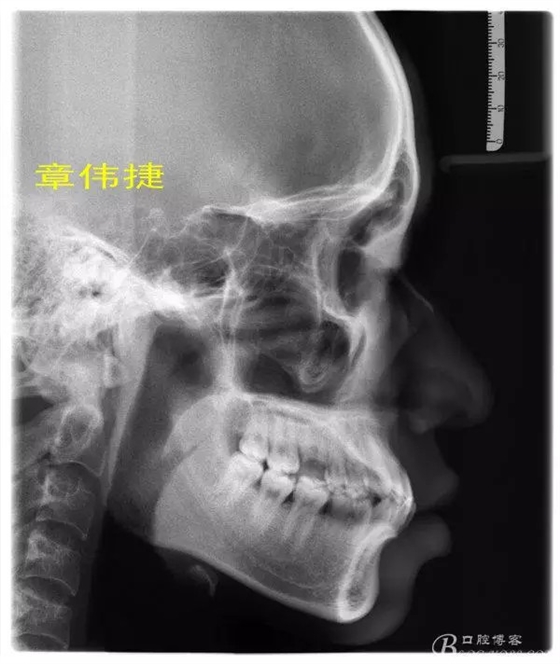

術(shù)前資料: